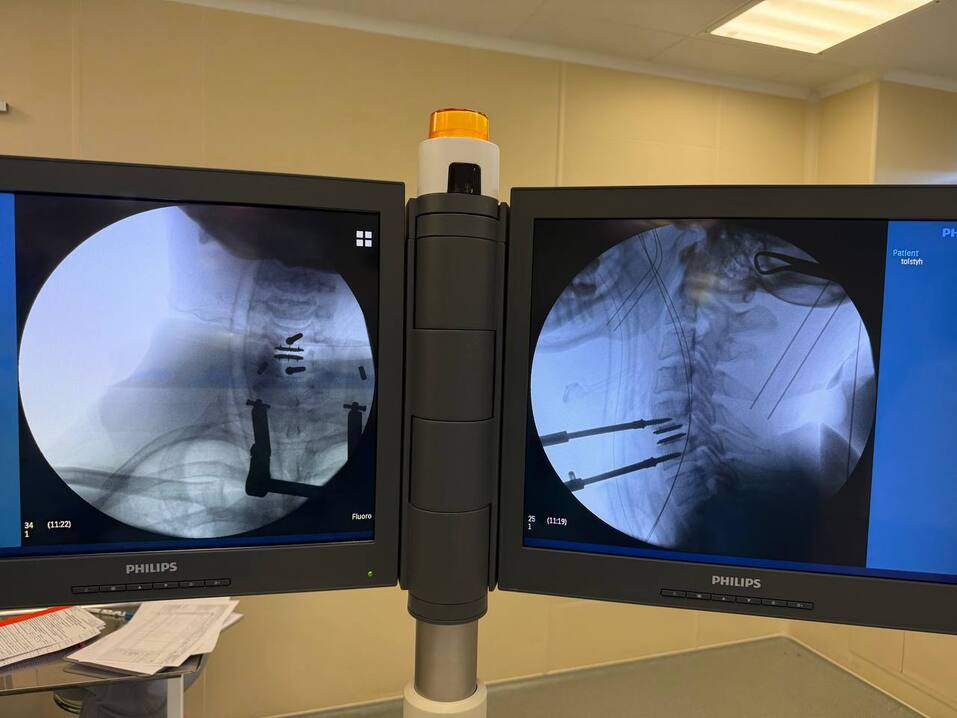

— Проведенную операцию мне не хотелось бы называть уникальной, она успешно проводится за рубежом и в России. Однако для Челябинской области операция является действительно новой. В шейном отделе позвоночника вмешательство выполнено впервые в нашем регионе. Вместо удаленного межпозвонкового диска мы устанавливали уже не «прокладку», а подвижный имплант. В международной практике подобные операции называют TDR — Total Disk Replacement. В русскоязычном варианте, наверное, правильнее было бы назвать эндопротезирование межпозвонкового диска. То есть его полная замена на работающий имплант. Это как сустав при крайней степени деградации. Его извлекли и установили имплант, который работает. Технически в этой операции ничего фантастического нет. Уникальность в самом импланте. Теперь они стали доступны и в России.

— У пациента средних лет присутствовала выраженная деградация диска, с формированием грыжи и остеофитов (костный нарост, который формируется на поверхности суставов. — прим. ред.), что привело к формированию специфических симптомов в верхних конечностях и в самой шее. Кроме того, было небольшое давление на спинной мозг, и в нижних конечностях отмечались определенные проблемы. Мы произвели полное извлечение диска, устранили все факторы, которые мешали его нервной системе, и установили подвижный имплант. Сейчас еще длится послеоперационный период, но пациент уже чувствует себя гораздо лучше.